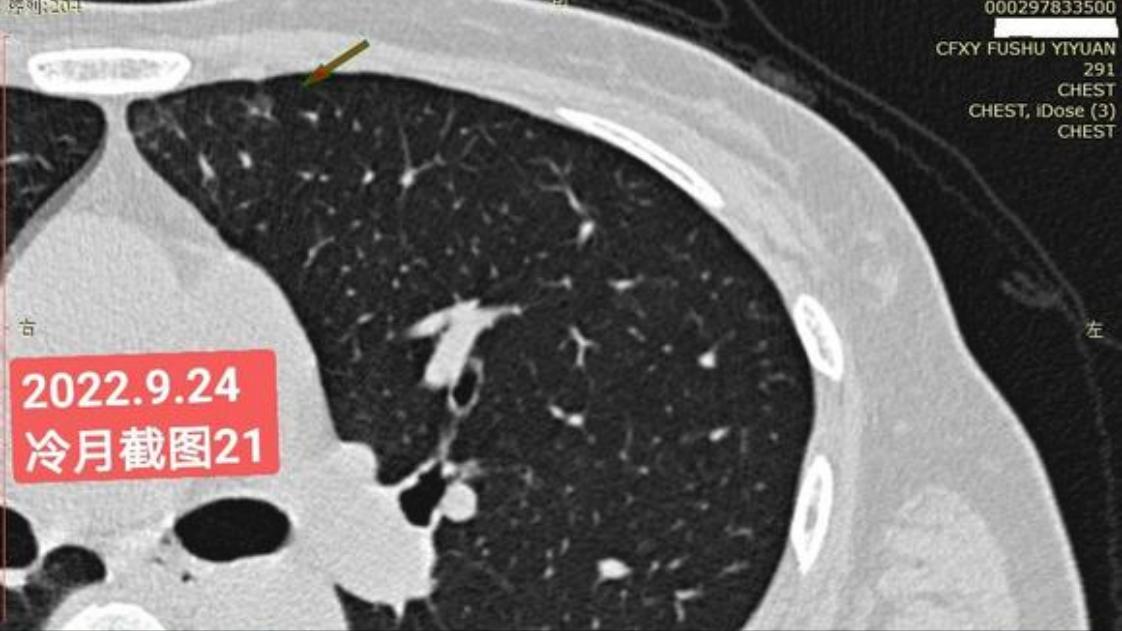

我是21年7月做肺部CT,报告给报出0.5厘米肺结节。(但大夫说,20年就已经有那个肺结节了,因为小,报告没给报)。自发现肺结节后,吃了四个月中药,结节没有缩小,反而增大了。今年8月1日开始到现在,又吃了近两个月的蒙药了。 结节还是没有缩小,反而在增大。21年7月到现在,复查过3次肺部CT了。结节一直在增大。最近一次复查时间是2022年9月24日。

上次找戴主任贴吧咨询过,主任说我右肺下叶那个结节高危,距离上次CT,到现在三个月复查肺部CT。所以9月24日又复查做了肺部CT。

右下肺结节高危,肺窗已经到亚实性阶段CTR>0.5,纵膈窗可见实性,目前已经不属于异质混磨,而且PSN亚实性结节。

谢谢您的信任和分享,结节小,7mm,没有高危因素,98%的根治率,不需要任何后续治疗,手术及时,没事了。